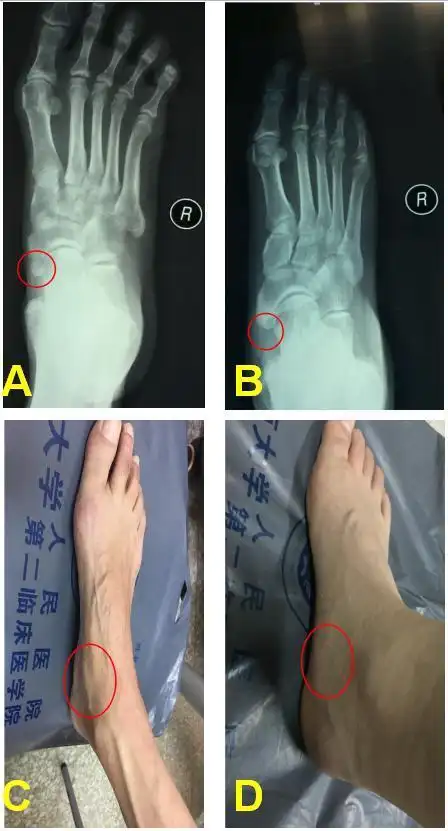

右脚足舟骨突出 一年了 现在走路疼痛 走久了就疼

答: 扭伤后出现的突出一小块骨头,这个一般是第一跖骨基底部撕脱骨折

正常的一只脚有7块跗骨,5块跖骨和14块趾骨,共计26块,但部分人由于